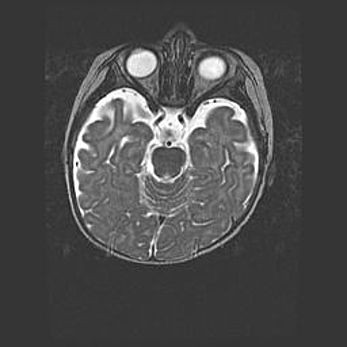

Открытая гидроцефалия.

Возраст: 9 месяцев 12 дней

Вес: 6800 г

Пол: мужской

Окружность головы: 41,5 см

Срок гестации: 28 недель

Гидроцефалия головного мозга у новорожденных имеет характерный признак: опережающий рост окружности головы приводит к визуально хорошо определяемой гидроцефальной форме сильно увеличенного в объёме черепа. Детские неврологи определяют следующие симптомы гидроцефалии у грудничков: выбухающий напряжённый родничок, частое запрокидывание головы, смещение глазных яблок к низу.